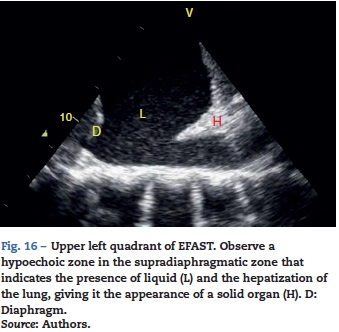

Pleural effusion should be searched for in the perisplenic and perihepatic quadrants of EFAST, moving two intercostal spaces in the direction of the head to locate the diaphragm.24 Normally, in the direction of the head from the diaphragmatic cupola there is a reflection of the spleen or the liver (Fig. 1C) while, in the presence of pleural effusion, a hypoechoic image can be observed and the lung compresses giving it the appearance of a solid organ (hepatization) (Fig. 16).24